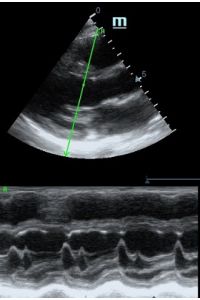

Но как же провести стандартные измерения в М-режиме, если мы его не использовали? На помощь приходит функция Free Xros M – анатомический М-режим. Имея записанную в память прибора видео петлю, мы можем провести линию М-режима в любом месте, при этом корректируя изначально не оптимальный угол.

TAPSE - показатель амплитуды движения латеральной части кольца трикуспидального клапана, позволяет количественно и быстро оценить систолическую функцию правого желудочка, норма которого составляет более 17 мм. Главным условием является проведение линии М-режима параллельно стенке правого желудочка в апикальном четырех камерном сечении, что легко достигается при Free Xros.